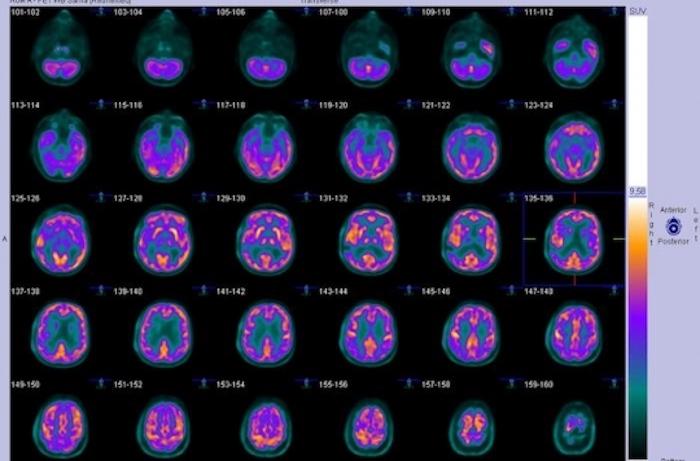

Des chercheurs ont mis au point une nouvelle méthode d’évaluation précoce de la réponse à un traitement antidépresseur à l’aide d'un PET scan, une technique particulière de scanner qui analyse la fixation d'un marqueur dans les zone actives du corps. Leurs résultats ont été publiés dans le Journal of Nuclear Medicine d’avril 2018.

Pour répondre à cet enjeu, des chercheurs américains ont développé une méthode d’évaluation par imagerie par tomographie par émission de positrons (TEP) qui pourrait permettre de prédire à l’avance si un traitement spécifique est susceptible d’être efficace pour le trouble dépressif majeur.

Le traceur mis au point par les chercheurs cible la protéine de transport de la sérotonine (5-HTT), une neurotransmetteur très impliqué dans la dépression, à l'intérieur d'une structure du cerveau, l’amygdale, qui fait partie des circuits cérébraux affectés par la dépression. Le TEP-scan permet de mesurer le taux de cette protéine avant et après le début du traitement antidépresseur, sachant que le taux de cette protéine est le reflet de la liaison entre 2 zones du cerveau critiques pour la dépression, le mésencéphale et l’amygdale. Or, les chercheurs ont constaté que chez les malades déprimés qui ne sont pas rémission après 12 mois de traitement, la liaison entre le mésencéphale et l’amygdale est plus faible.

Un PET-scan peut donc indiquer, selon le taux de 5-HTT mesuré avant le traitement, quels patients seront améliorés par le traitement. Par ailleurs, la quantification de la liaison entre le mésencéphale et l'amygdale cérébrale sous traitement pourrait constituer un biomarqueur potentiel pour la rémission après traitement antidépresseur.